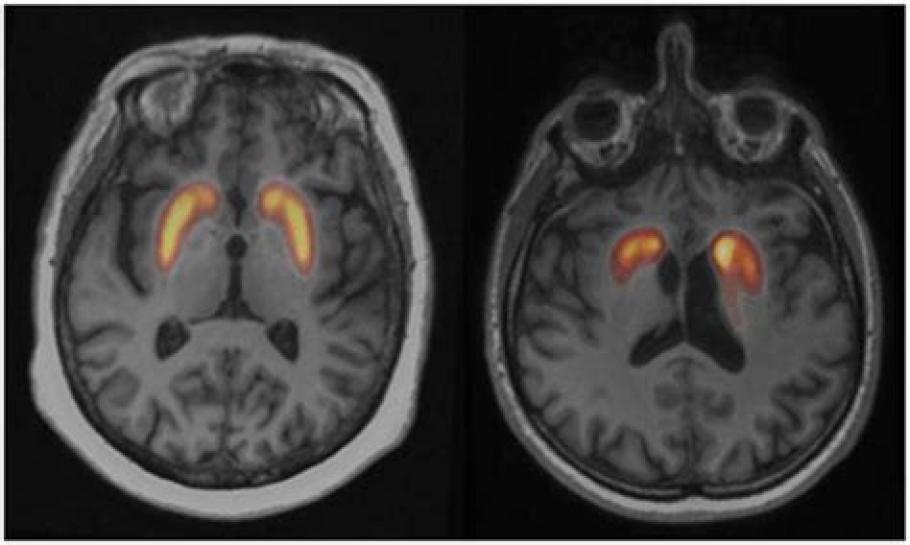

Cet examen d’imagerie en médecine nucléaire vise à évaluer l’activité du transporteur de la dopamine dans le cerveau. Son interprétation est généralement binaire : normale ou pathologique — environ un tiers des examens sont normaux, et deux tiers montrent une anomalie.

L’analyse repose principalement sur des critères morphologiques visuels (comme l’asymétrie ou le gradient d’intensité), parfois complétés par des mesures semi-quantitatives (ratios de fixation).

Ces examens, réalisés en imagerie tomographique par émission monophotonique (TEMP), permettent d’explorer le transporteur de la dopamine, un marqueur essentiel dans le diagnostic des syndromes parkinsoniens.